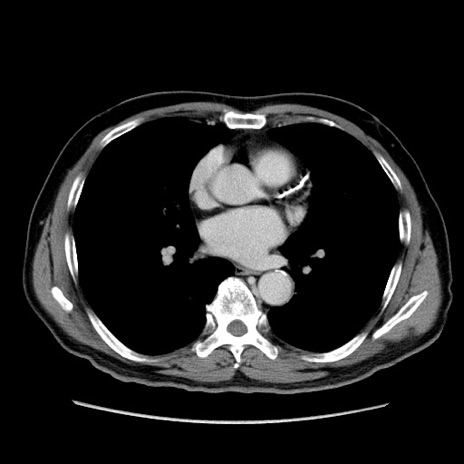

症例34(横断像)

【症例】60歳代 男性

【主訴】右鼠径部膨隆

【現病歴】1年程前より右鼠径部膨隆あり。自己にて還納可能だったため放置していた。3時間前より右鼠径部の脱出を認め、還納困難となり受診。

【既往歴】高血圧

【身体所見】右鼠径部に小児頭大の膨隆あり。弾性硬であり、用手還納は困難。左鼠径部にも膨隆を認める。脱出はなし。

【データ】WBC 15500、CRP 測定なし